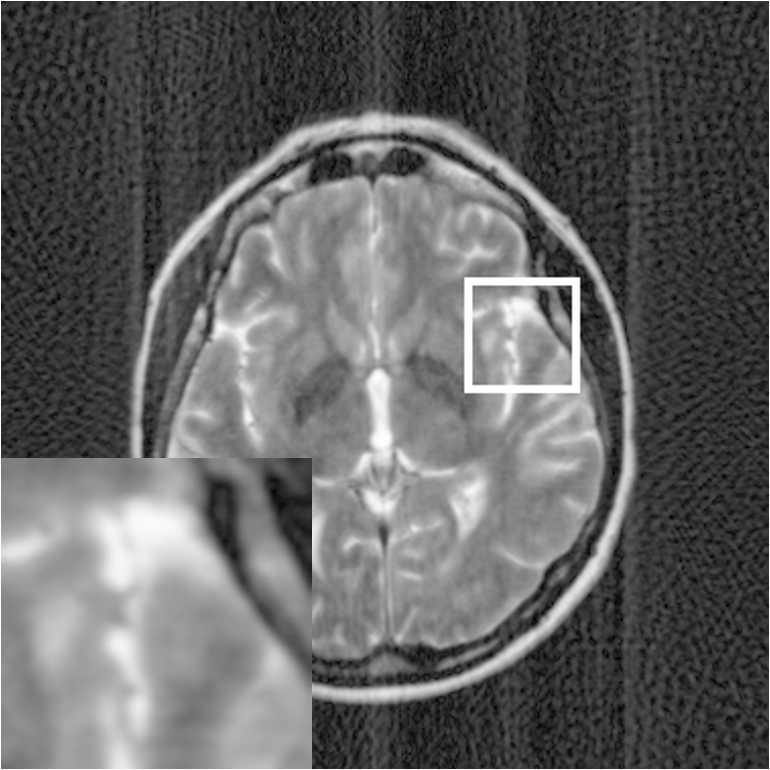

Figure 7: Reconstruction results for 20% variable density sampling. (a) Original. (b)-(h) Reconstructed images. (i)-(n) The errors of six CSMRI methods.

As shown in Figs. 7, 8 and 9, Sparse MRI and DLMRI have a lot of unpleasant artifacts, Residual learning and U-net can eliminate most of artifacts, but are not ideal for restoring image details. However, the proposed method can reconstruct better MR images, which outperforms other competitive methods in visualization of structures reconstruction and artifacts removal. Meanwhile, we can see from the absolute error residuals for three sampling experiments that the proposed MDN algorithm restores a finer detail structure than other algorithms. Moreover, we present the PSNR and SSIM values in Table I for different algorithms, sampling masks and sampling rates. It is demonstrated that the proposed method provides better reconstruction performance and visual results than other competitive methods. We can also see the obvious improvement of all algorithms over zero-filling both in visualization. In particular, a higher SSIM value of Sparse MRI appears when using 30% variable density random sampling, however, Sparse MRI generates more artifacts than the proposed MDN.